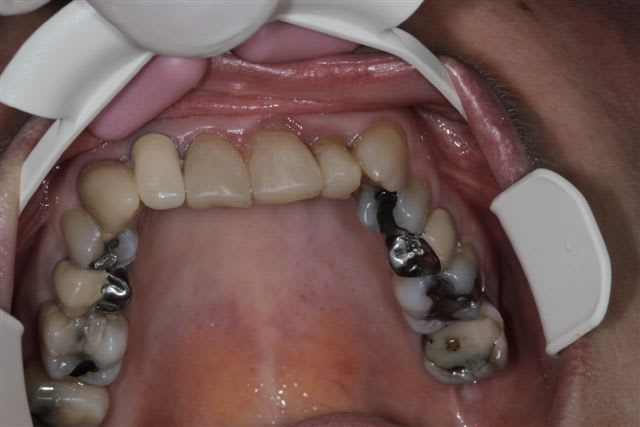

La suite, les soins ont commencés le 07/08.

Postérieur bas (16/08)et haut (14/09) en place, essayage des Emax avec "cutback".

Pour la teinte la patiente exige B1, sans maquillage, elle n'a pas attendu 47 ans pour que ça ne soit pas Blanc de blanc, alors là dessus j'ai cédé.

Cas typique de patient refusant l'ortho avant la réhabilitation global, avec un résultat esthétique ....disons que j'aime pas, bon si la patiente est contente!

Moi en tout cas au prochain patient qui refuse l'ortho nécessaire avant la réhabilitation globale, je lui montre ce cas. Merci encore je pense que cela sera utile.

Peut-on encore à ce stade diminuer (fortement) le volume des canines, réaligner les faces vestibulaires des PM droites, augmenter le volumes des centrales et distaliser les latérales???

Une petite élongation coronaire sur 11 et 21 n'aurait pas été de refus si racine pas trop courte.

1) la patiente a une paralysie faciale (levre superieure gauche). Le fait que les canine-premolaires-molaires cote II soient plus longues que les incisives accentue ce probleme.

Je raccourcirais ttes les dents de 23 à 26 de 2mm.

2) Axe de 13 pas bon. trop de bombe vestibulaire. Peut etre que la dent n'est pas assez taillee. En tout cas je la trouve trop dominante dans le sourire.

Les 2 canines sont effectivement très massives... Après tu fais avec les moyens que la patiente te donne, évidemment, mais là pour le coup je trouve pas ça très beau non plus.